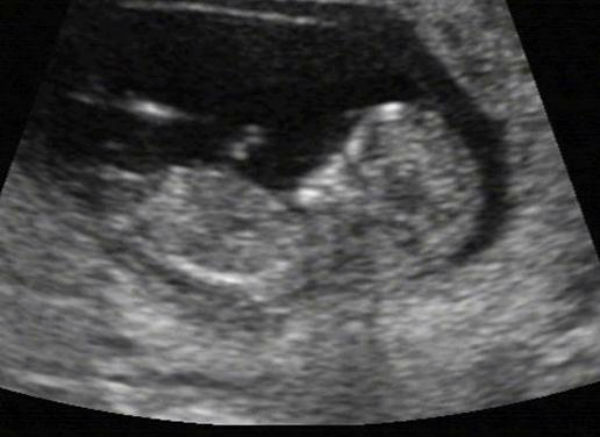

영국 노팅엄, 애든버러, 글래스고, 애버딘 대학 공동연구팀은 과학뉴스 ‘메디컬익스프레스’를 통해 임신 중 흡연이 12~20주 태아의 간 세포에 유전자 변이의 일종인 ‘DNA 메틸화’를 일으킨다고 30일 밝혔다.

연구팀에 따르면 임신 중 흡연은 신체의 주요기관인 간장의 발달에 부정확한 프로그램을 입력시켜 남성 태아의 간 기능을 여성 태아처럼, 여성 태아의 간 기능을 남성 태아처럼 변이시킨다.